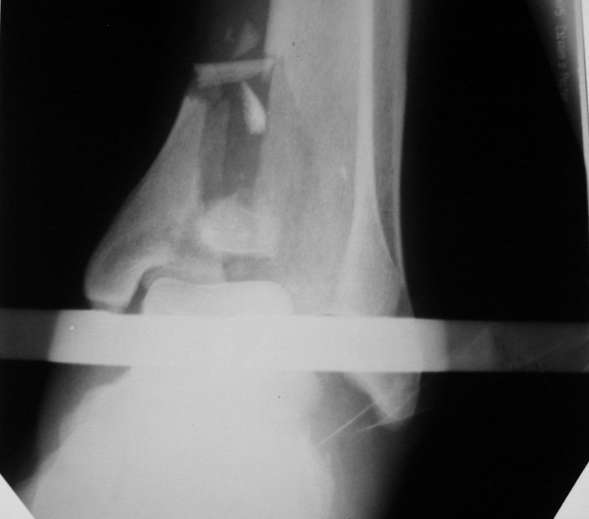

Здравствуйте, коллеги.Больной 26 лет, в 2004 году попал ко мне с диагнозом:синтезированный в аппарате Илизарова неполный внутрисуставной оскольчатый перелом дистального метафиза левой большеберцовой кости со смещением; выраженный остеопороз; множественное спицевое нагноение. Несостоятельность фиксации (костные отломки буквально "елозили" по спицам, несмотря наналичие упорных площадок).

Мной был демонтирован АВФ, удалены все спицы. Больной некоторое время лечился консервативно (шина Белера, антибиотики, перевязки). По заживлению и купировании гнойно-воспалительного процесса была произведена осткрытая репозиция, накостный остеосинтез 1/3 трубчатой пластиной.Такой вариант был принят из-за жуткого остеопороза и отказом больного от предложенного артродезирования голеностопного сустава сразу. Послеоперационный период без особенностей. Через год, больной пришел на осмотр на своих двоих, без дополнительной опоры, с жалобами на боли приходьбе в обл. г/стопа и с желанием замкнуть сустав. В операционной столкнулся с неожиданной проблемой по удалению пластины, она была глубоко вмурована в толщу склерозированного метафиза на глубину 1.5 см; удалить не рискнул (считал, что металл помешает в ходе реконструкции и требуется его удаление).

Было решено, уже по ходу операции, выполнить артродез болтом-стяжкой, тем самым компрессируя резецированные суставные поверхности и смещая стопу латерально, дабы нивелировать варусную деформацию и восстанавливая тем самым опорную ось всей конечности.

Вчера (прошло около 8 месяцев)больной обратился ко мне в очередной раз с жалобами на боли умеренно-жгучего характера в области выстояния концов болта-стяжки. На момент осмотра:укорочение левой нижней конечности на 1,5 см; гипотрофия медиальной группы мышц голени и четырехглавой мышцы бедра; передвигается без дополнительной опоры в ортопедической обуви на растояние до 5 км; работает приемщиком цветных металлов (приходится перетаскивать грузы). Нарентгенограмме, насколько это можно видеть, костного блока сформировать не удалось, но движений в голеностопном суставе нет - ни активных, ни пассивных. Послеоперационные рубцы б/о; свищей и нагноения не было. Активно больногонаблюдать не приходилось, т.к. проживает в другом городе.

ЗЫ: Прошу прощения за очень низкое качество представленных ренгенограмм. Буду очень признателен за комментарии.